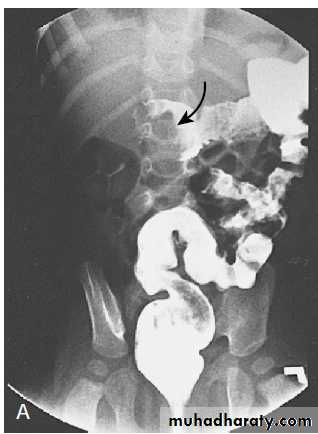

3. Contrast enema